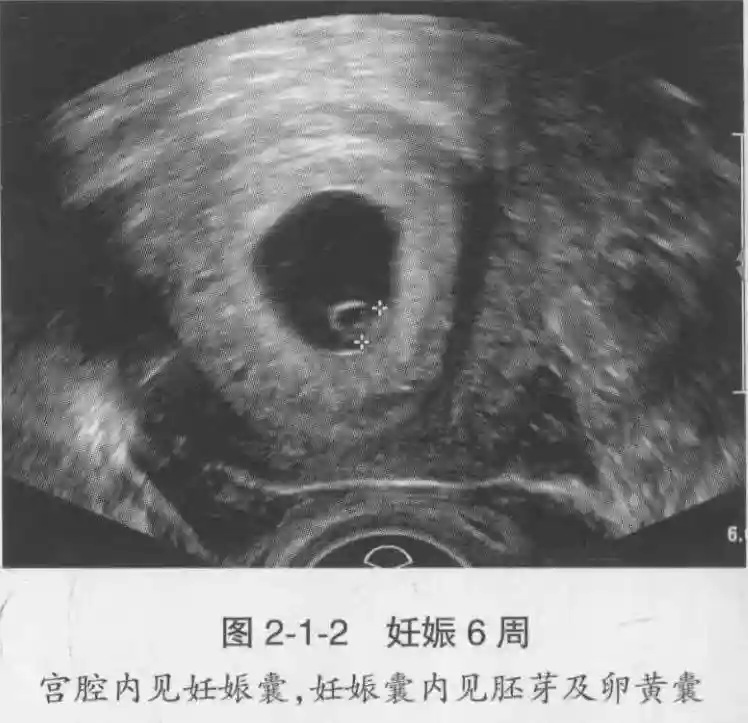

3??胚胎:胚胎通常在6-7周时可以为超声显示,起初为胎芽,表现为卵黄囊一侧局部组织增厚,达到1 -2 mm 时才有可能为超声测量出来。达4-5mm时可见胎心搏动,相应孕周为6-6.5周,妊娠囊大小为13-18mm。胚芽长度≥7㎜时仍未见心管搏动,提示胚胎停止发育。胚胎的出现和妊娠囊直径的关系:妊娠囊直径> 16 mm 时,经阴道超声应显示胚胎。妊娠囊直径> 25 mm 时,经腹超声均应显示胚胎。

4??胎心搏动:胎心搏动通常出现于6-6.5周,胚胎在4- 5mm就应该显示胎心搏动。